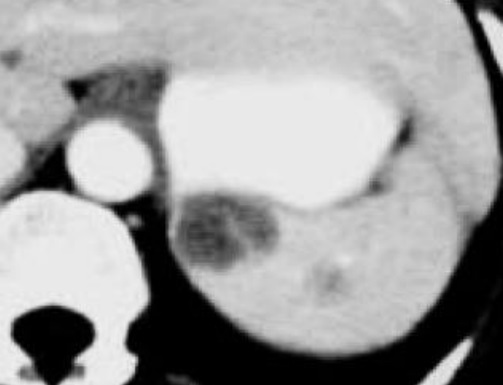

Image radiologique TDM d'une

non Hogdkiniens lytmphoma de la rate . Aspect

lesionel est une masse unique isolée ovalaire

hypodensite , homogene à biên

limite de la rate |